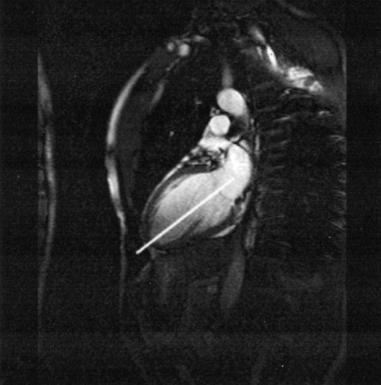

The right atrium forms the right border of the heart and receives deoxygenated blood from the body via the superior and inferior venae cavae and from the coronary sinus and cardiac veins that drain the myocardium. A small muscular embryonic appendage, the right auricle, projects upward and toward the left from the right atrium, covering the root of the aorta (Figure 6.40). The right ventricle lies on the diaphragm and comprises the largest portion of the anterior surface of the heart. It receives deoxygenated blood from the right atrium and forces it into the pulmonary trunk for conveyance to the lungs. Projecting off the inferior surface of the ventricular walls are conical-shaped projections of cardiac muscle called papillary muscles that anchor the cusps of the tricuspid valve to the right ventricle (Figure 6.39). The left atrium lies posterior to the right atrium and is the most posterior surface of the heart. It also has an embryonic appendage, the left auricle, that projects to the left of the pulmonary trunk over the superior surface of the heart. The left atrium receives oxygenated blood directly from the lungs via the four pulmonary veins (two on each side). The left ventricle forms the apex, left border, and most of the inferior surface of the heart. It receives oxygenated blood from the left atrium and pumps it into the aorta for distribution throughout the systemic circuit. The myocardium of the left ventricle is normally three times thicker than that of the right ventricle, reflecting the force necessary to pump blood to the distant sites of the systemic circulation (Figures 6.41 through 6.52). Two papillary muscles project from the ventricular walls to anchor the bicuspid valve to the ventricle (Figures 6.39 and 6.47).

Figure 6.43 Axial, T1-weighted MR scan of left atrium.

Key: RV, Right ventricle; LV, left ventricle; LA, left atrium; RA, right atrium.